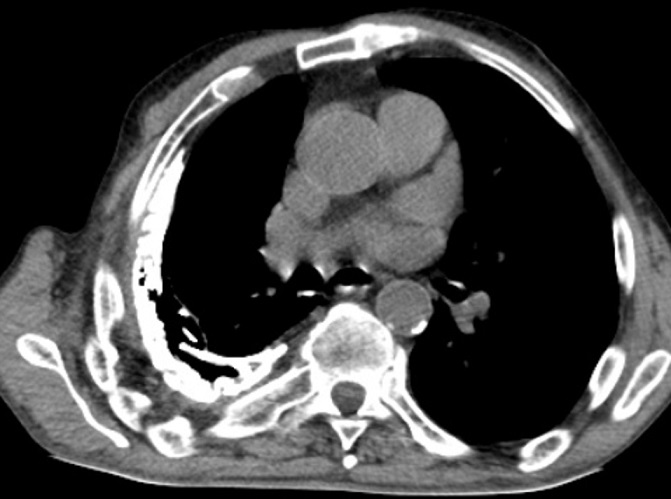

Mệme cas en coupe TDM axiale

avec aspect radiologique en plaque diffuse

hyperdensite de la plevre du poumon droit . Poumon

droit est en un peu de restrictive par la lesion de

tuberculose |